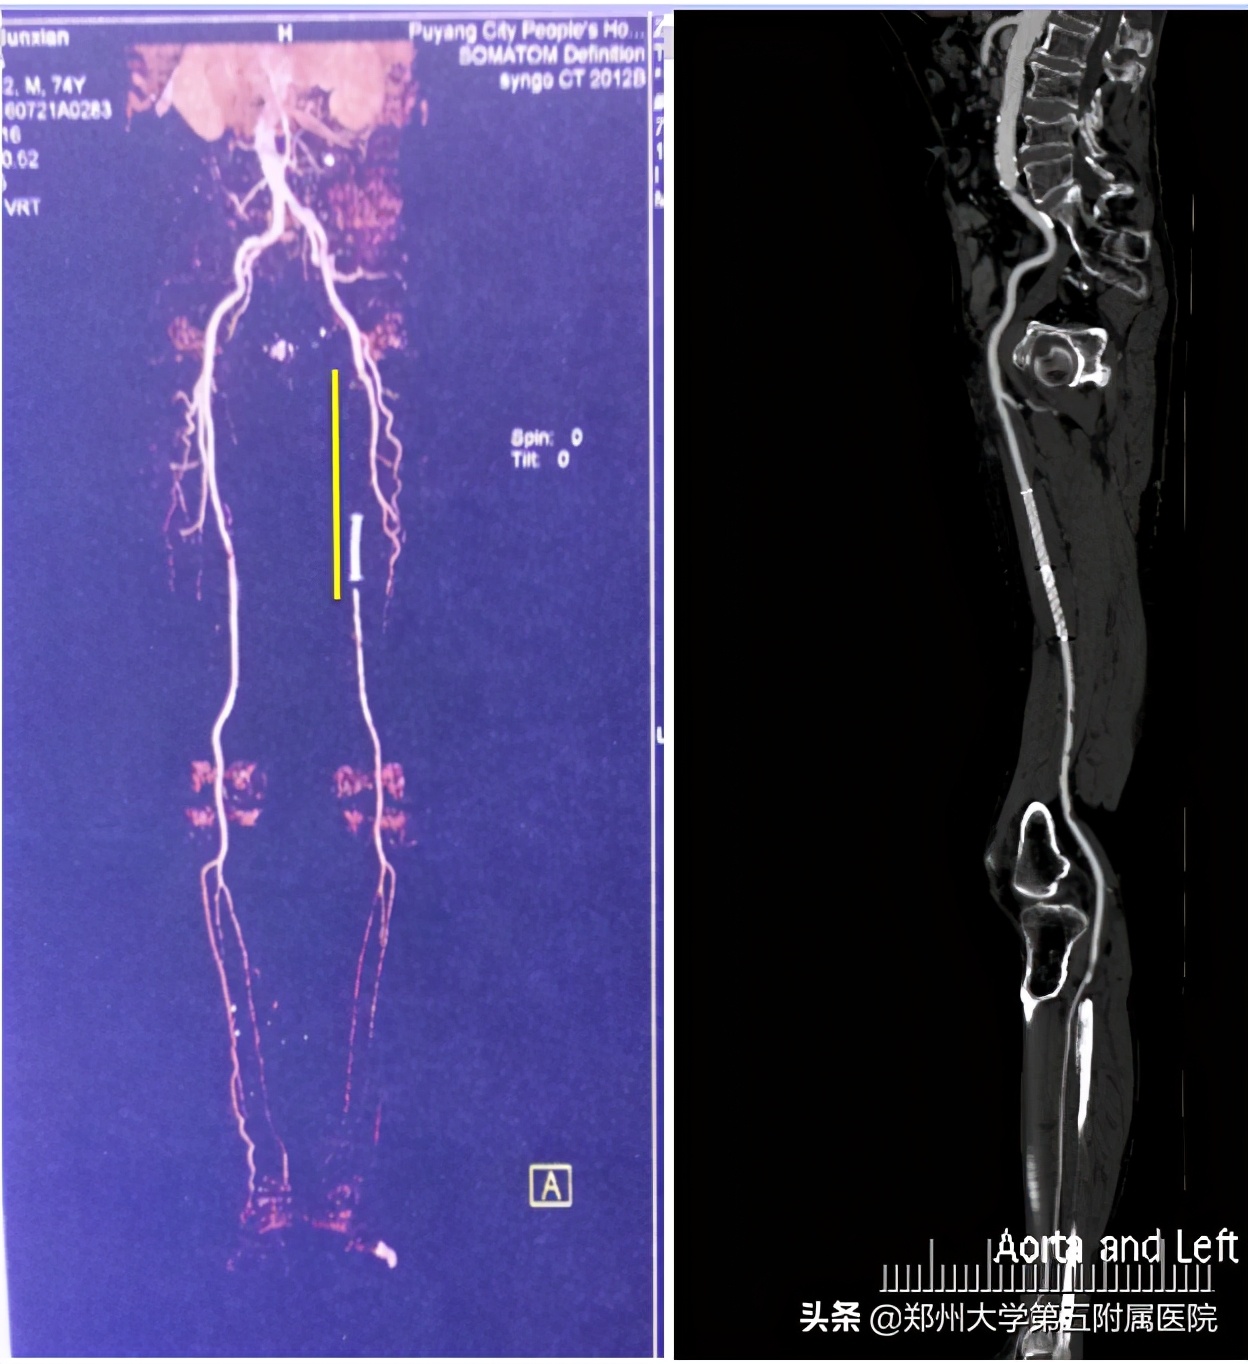

▲ 下肢动脉闭塞支架植入后自行停药,血管再闭塞,经手术处理后恢复通畅